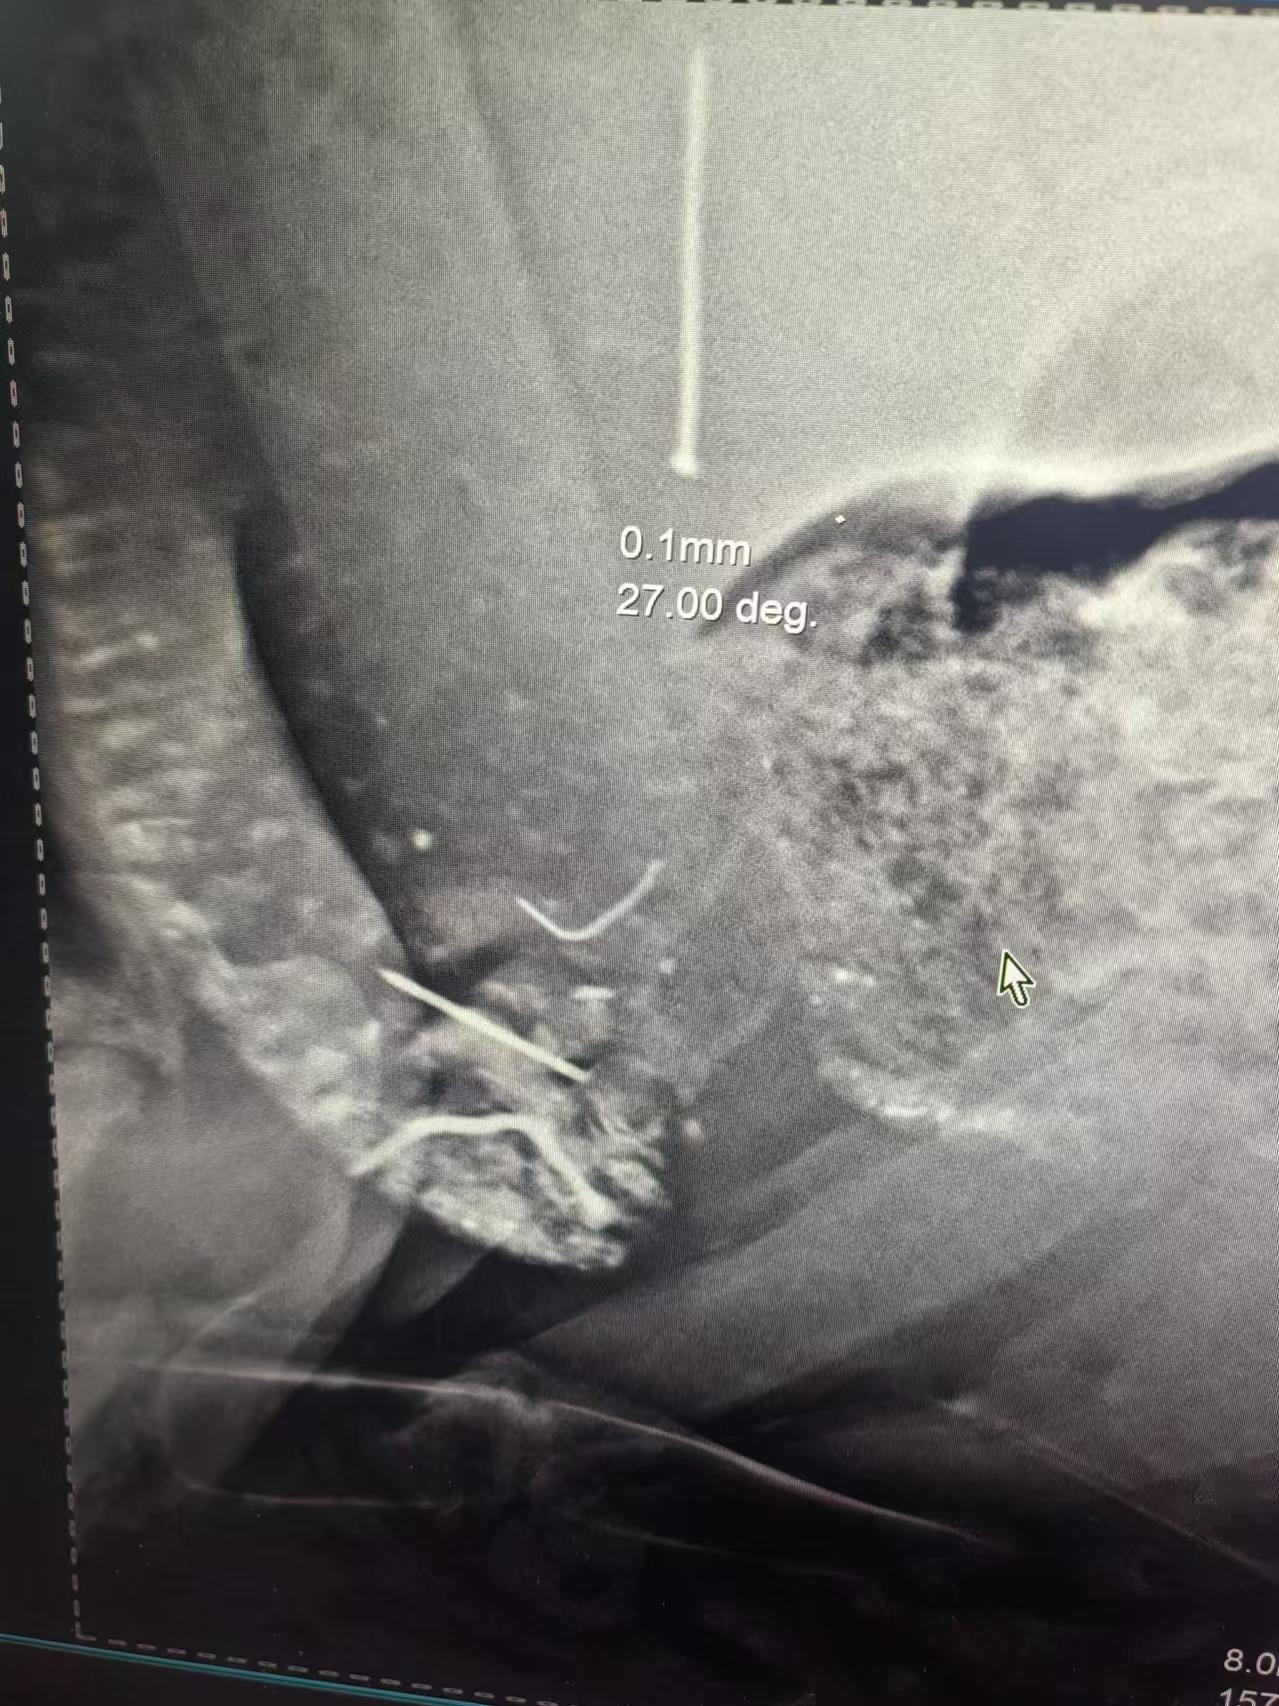

在动物医疗方面,其产品有着广泛的应用。首先是宠物医院临床应用,公司的宠物专用DR影像设备已在国内多家宠物诊疗机构投入使用,可用于猫狗等常见宠物的骨折、肺部感染、泌尿系统结石等疾病的影像诊断。设备搭载图像增强软件工具包,可自动优化对比度与边缘清晰度,帮助兽医快速识别病灶。其次是大型动物健康监测,针对牛、马、大象等大型动物,公司研发的大动物专用DR数字化影像系统具备400毫安超大功率发生器和进口X射线球管,穿透力强,成像稳定,已在部分畜牧养殖基地和野生动物保护区应用,支持野外移动出诊与规模化健康筛查。

成像质量优异也是其显著特点。公司优化了图像处理算法,有效过滤金属外壳干扰、噪声等因素,显著提升缺陷识别准确率与诊断可信度。并且支持DR数字化成像,实现快速出图、远程传输与数据存档,适配现代医疗与工业数字化管理流程。